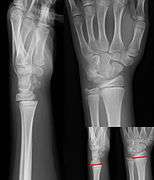

Salter–Harris fracture images

| Salter–Harris fracture radiographs with insets showing fracture lines. | ||||||||